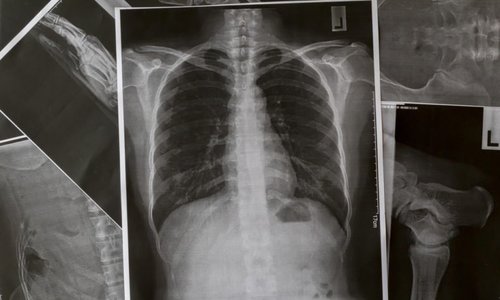

Chóng mặt, khó thở, đau ngực, đau chân hay ho ra máu là những triệu chứng phổ biến của thuyên tắc phổi.